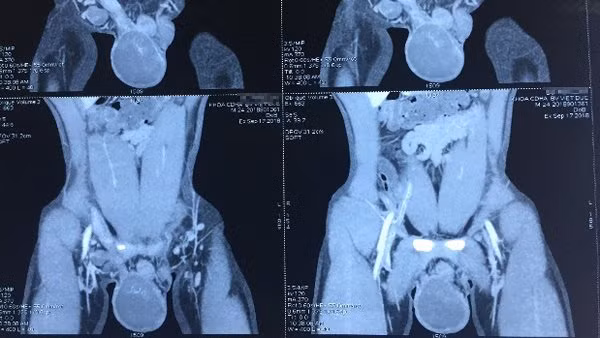

Kết quả kiểm tra cho thấy, bệnh nhân có tinh hoàn phải to chắc, ấn đau, biến đổi hình thái, tinh hoàn trái nhỏ. Hình ảnh chụp CT chỉ rõ hình ảnh u tinh hoàn phải chưa xâm lấn ra vỏ tinh hoàn và các tổ chức lân cận.

![]() |

| Hình ảnh khối u trên tinh hoàn phải của bệnh nhân |